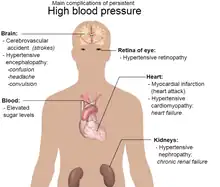

Hypertension is a condition characterized by an elevated blood pressure in which the long term consequences include cardiovascular disease, kidney disease, adrenal gland tumors, vision impairment, memory loss, metabolic syndrome, stroke and dementia.[1] It affects nearly 1 in 2 Americans and remains as a contributing cause of death in the United States.[2] There are many genetic and environmental factors involved with the development of hypertension including genetics, diet, and stress.

The brain is one of the major organs affected by hypertension and recent findings have linked hypertension to various forms of cognitive decline. Not only does hypertension affect the cellular structure and molecular composition of blood vessels (arteries, veins, capillaries), it also affects their ability to regulate vital functions that are essential for healthy brain function such as oxygen and glucose delivery, cerebral environment control via the blood-brain barrier, and trafficking of immune cells and metabolic by-products.[3] These hypertension-induced effects eventually lead to white matter lesions, which is the pathological basis for hypertension-induced cognitive impairment.[4] A National Institute on Aging (NIA) study that measured cognition twenty years after measuring blood pressure showed that there was a 9% increase in risk for cognitive decline for every 10mmHg increase in systolic blood pressure.[5] Additionally, the Atherosclerosis Risk in Communities cognitive study shows that those with prehypertension or high blood pressure performed lower on processing speed, short-term memory, and executive function tests.[5] Hypertension is also a prominent risk factor for two major brain diseases: stroke and dementia, and accounts for approximately 50% of deaths caused by stroke or heart disease according to the World Health Organization (WHO).